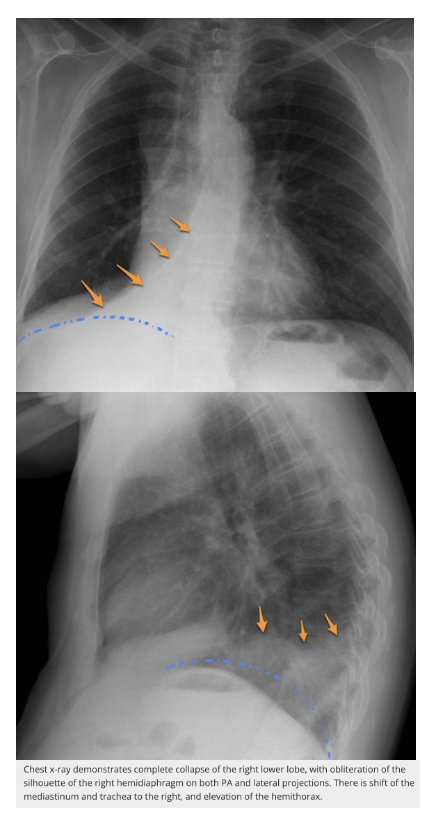

What are the features of RLL collapse on CXR?

A

CXR features: (7)

Triangular opacity in RLZ medially with apex pointing toward R hilum

Obscured medial R hemidiaphragm

Inferior displacement of the right hilum

Obscured descending interlobular pulmonary artery

Distinct R heart border

Inferior displacement of horizontal fissure

Elevation of R hemidiaphragm

Crowding of R sided ribs

Shift of mediastinum to the right

Lateral CXR:

Triangular opacity in lower posterior chest

Obscured post R hemidiaphragm

Increased attenuation over the lower thoracic vertebrae

Oblique fissure displaced posteroinferiorly

Inferior displacement of R hilum